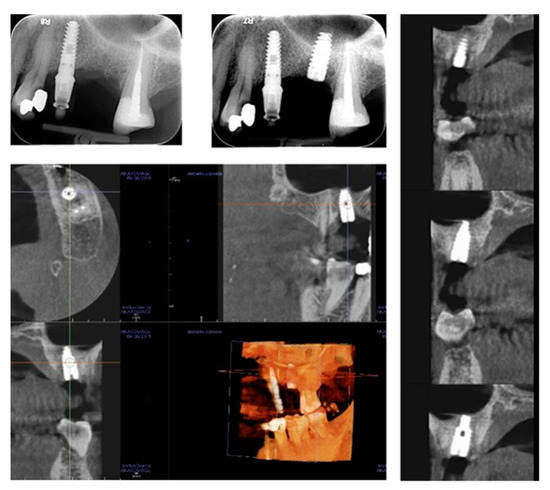

In all cases, fixtures were placed with high insertion torque (up to 50 Ncm) and with atraumatic crestal lifting of the sinus membrane (Figure 2a–c and Figure 3a–f). Prostheses were placed 3 months after surgery; more precisely, 40 were cemented metal–ceramic crowns, and the remaining were screwed hybrid ceramic crowns (Vita Enamic Multicolor) with glued titanium bases (Figure 4). All implants had a diameter of 4.2 mm, and 35 were 6.25 mm in length, while the remaining 45 had a length of 8 mm (Figure 5).

Figure 5. Radiological investigations showing the pre-surgical planning of the crestal sinus lifting and the radiological result after implant insertion; the elevation of sinus membrane is evident, and no signs of intra-sinusal inflammation are detectable after surgery.